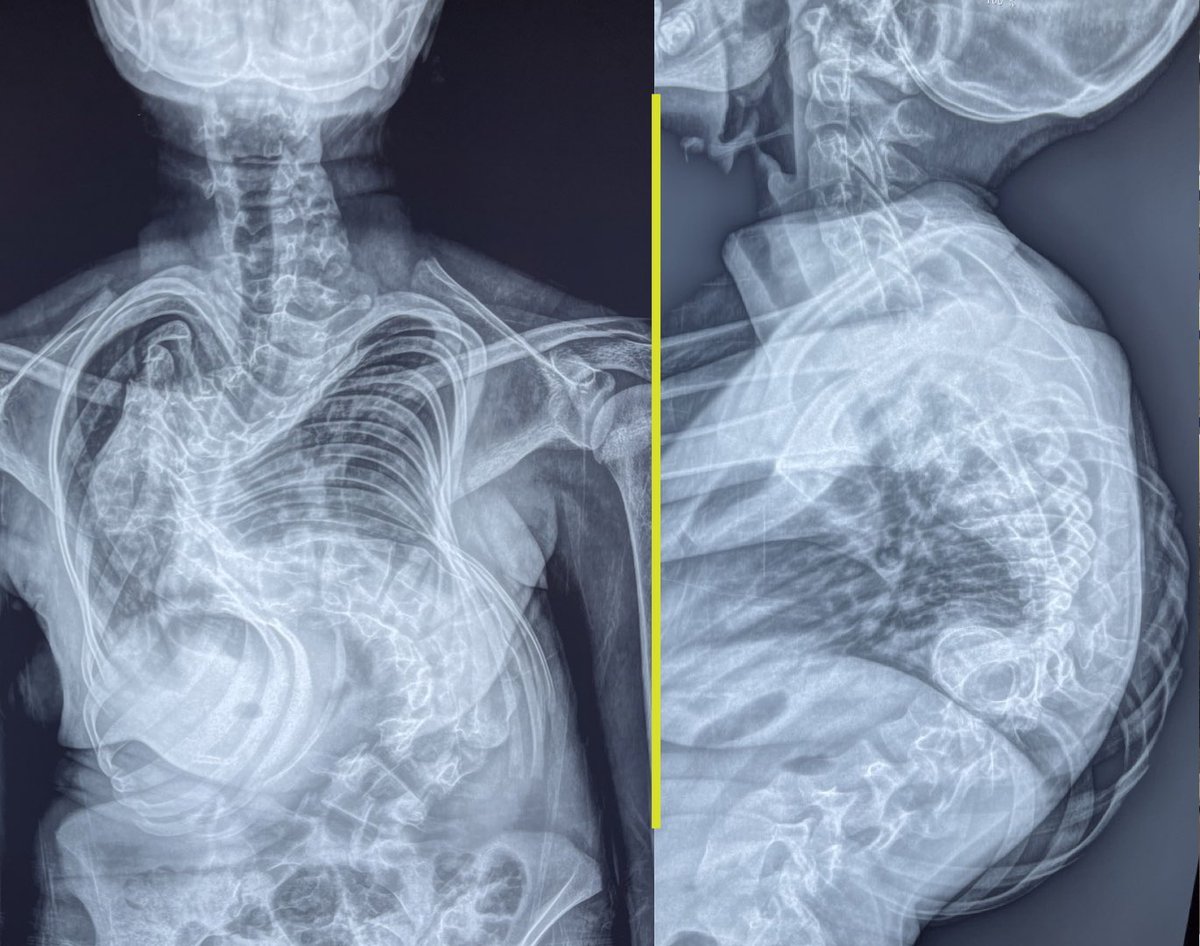

كان عندها تشوه رهيب و دي كانت الاشعه اللي ممكن تفسر موقفها و كان عندها قصة معانآه رهيبه و دخلوها العمليات قبل كدا و خرجوها بدون عمليه نظراً للخطورة الشديده و الدنيا كانت مقفله كل الابواب…. المهم عملتلها العمليه من ٦ شهور و ربنا اكرمنا جامد و اصبحت هدي واحدة تانيه خالص …